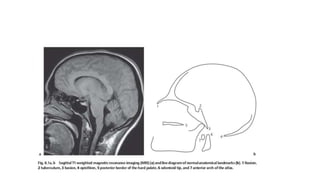

McGregor’s line (basal line)

Line drawn from posterior tip of

Hard palate to lowest part of

Occiput